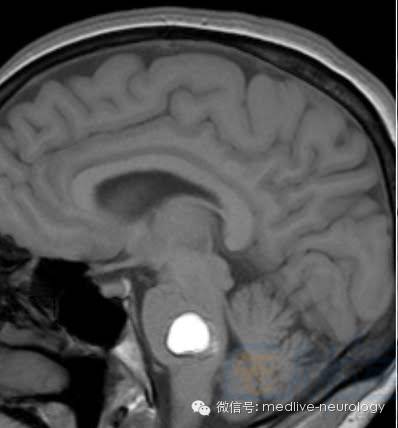

亚急性早期(3-7d): 脑桥